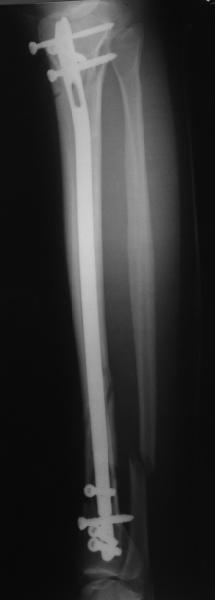

There are some more tricks which allow not to plate the fibula and provide good alignment and stability. A small wire distractor can provide alignment and restore length of both tibia and

fibula. Angular stability of the tibia is provided by insertion of more than two conventional medial-lateral locking screws. To maintain the position of the fibula perQ insertion of a single position screw often could be enough. I bet the articles didn't analyze the options.

A typical case is attached, also an image with intra-op reduction obtained by a small wire distractor, in the moment of insertion a Poller wire in AP direction. Fixation by a SIGN nail. Despite the fibula was not fixed healing was obtained with the unchanged alignment.

In this particlar case 4 frontal wires were inserted in anterior and posterior aspects at both sides of proximal fracture, and fixed to a single half ring with some bend to provide compression with wire tension. Image attached.

На одной опоре, расположенной чуть дистальнее обычного, были закреплены 4 спицы, проведенные во фронтальной плоскости, по 2 в передней и задней части смежных фрагментов. Закреплены так, чтобы при их натяжении создалась компрессия. Картинка в приложении.